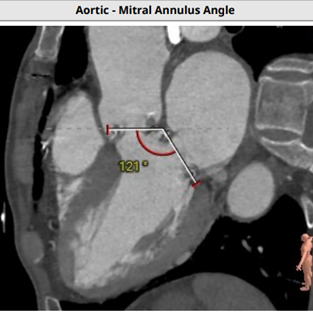

投照角度(LAO 14,CRA 1)、左室二尖瓣轴线角度(121度)和入路角度(153度):